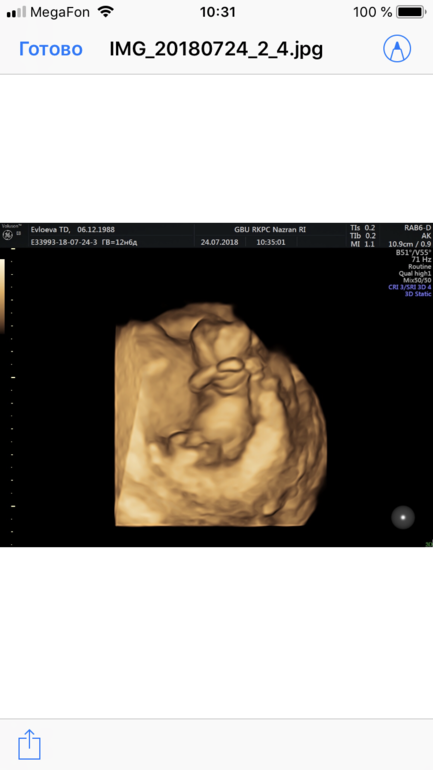

Изображение Как думаете кто?

Как думаете кто здесь мальчик или девочка ?)

02.08.2018